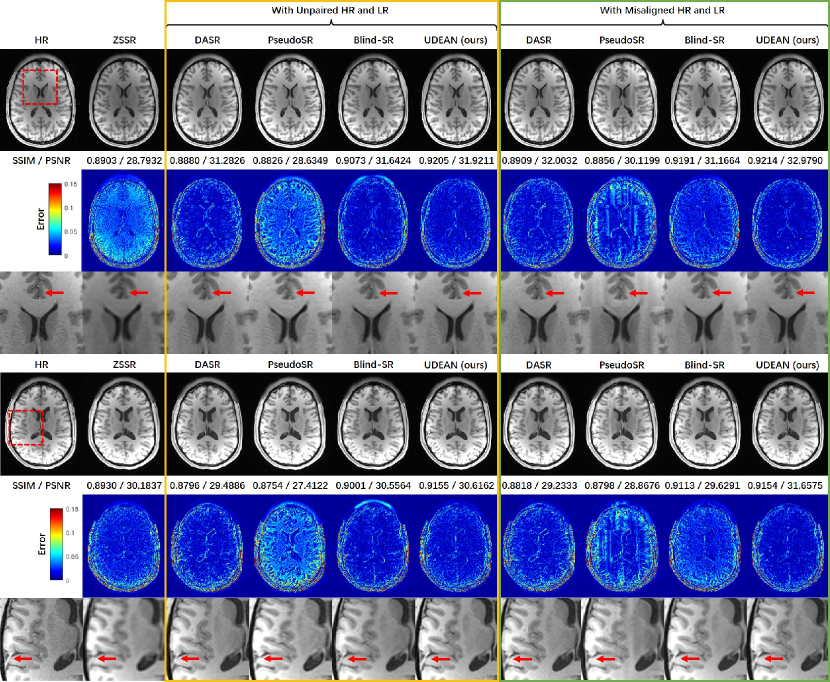

We implemented other state-of-the-art unsupervised networks, including ZSSR [18], DASR [23], PseudoSR[22], and Blind-SR[24], as the baseline. All these networks used the same backbone as the UDEAN for both generators and discriminators and trained with identical training setups, including training datasets and hyperparameters, for fair comparisons. For inference, UDEAN and DASR used a single upsampling network with the same structure. As a result, the inference process for UDEAN and DASR consumed identical computation resources, including the same number of network parameters, number of operations, GPU consumption, and inference time. Blind-SR and PseudoSR used another network for style transfer in addition to the upsampling network, thus consuming approximately twice as many computation resources as the other two. The numerical results in Table 2 reveal that the UDEAN outperformed all the above-mentioned networks for MRI SRR from both misaligned and unpaired training data, which are from two public datasets with different contrasts and two scale factors. Specifically, for the HCP dataset and both scale factors, UDEAN outperformed the other networks in the SSIM and PSNR values for both misaligned and unpaired training data, only except the PSNR value of ZSSR with the scale factor of . For the BraTS dataset, the UDEAN also outperformed all the other networks with the highest SSIM and PSNR values in most of the experiments.

As to the qualitative comparison shown in Fig. 6 for the SRR of the HCP dataset with a scale factor of , ZSSR generated highly blurry images, although its metrics values are higher than DASR and PseudoSR in some cases. Among all the images, the ones reconstructed by UDEAN achieved the lowest errors as shown in the error maps, and the best accuracy in small anatomical structures pointed out by the red arrows. Also shown in Fig. 7 for the SRR with the BraTS dataset and the scale factor of , UDEAN achieved better accuracy than the other networks in the structures of lesions, which may improve the accuracy of the assessment of the lesions and the therapy based on the reconstructed SR images.